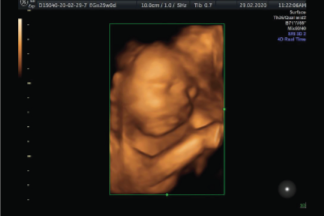

Una Ecografía Estructural ayuda a evaluar detalladamente al bebé, se realiza con la combinación de la ecografía de alta definición Doppler Color, el 4D y el 5D. Es recomendable se realice de la semana 20 a la 23 con el fin de detectar anomalías anatómicas fetales.

La Ecografía estructural realizamos la medición de tu bebé, medición de líquido amniótico , localización y evaluación placentaria, revisamos cada órgano de tu bebé cara, ojos, hueso nasal, boca, cráneo, cerebro, tórax, corazón, pulmones, abdomen, pared abdominal, riñones, estómago, hígado, vejiga, columna y extremidades.